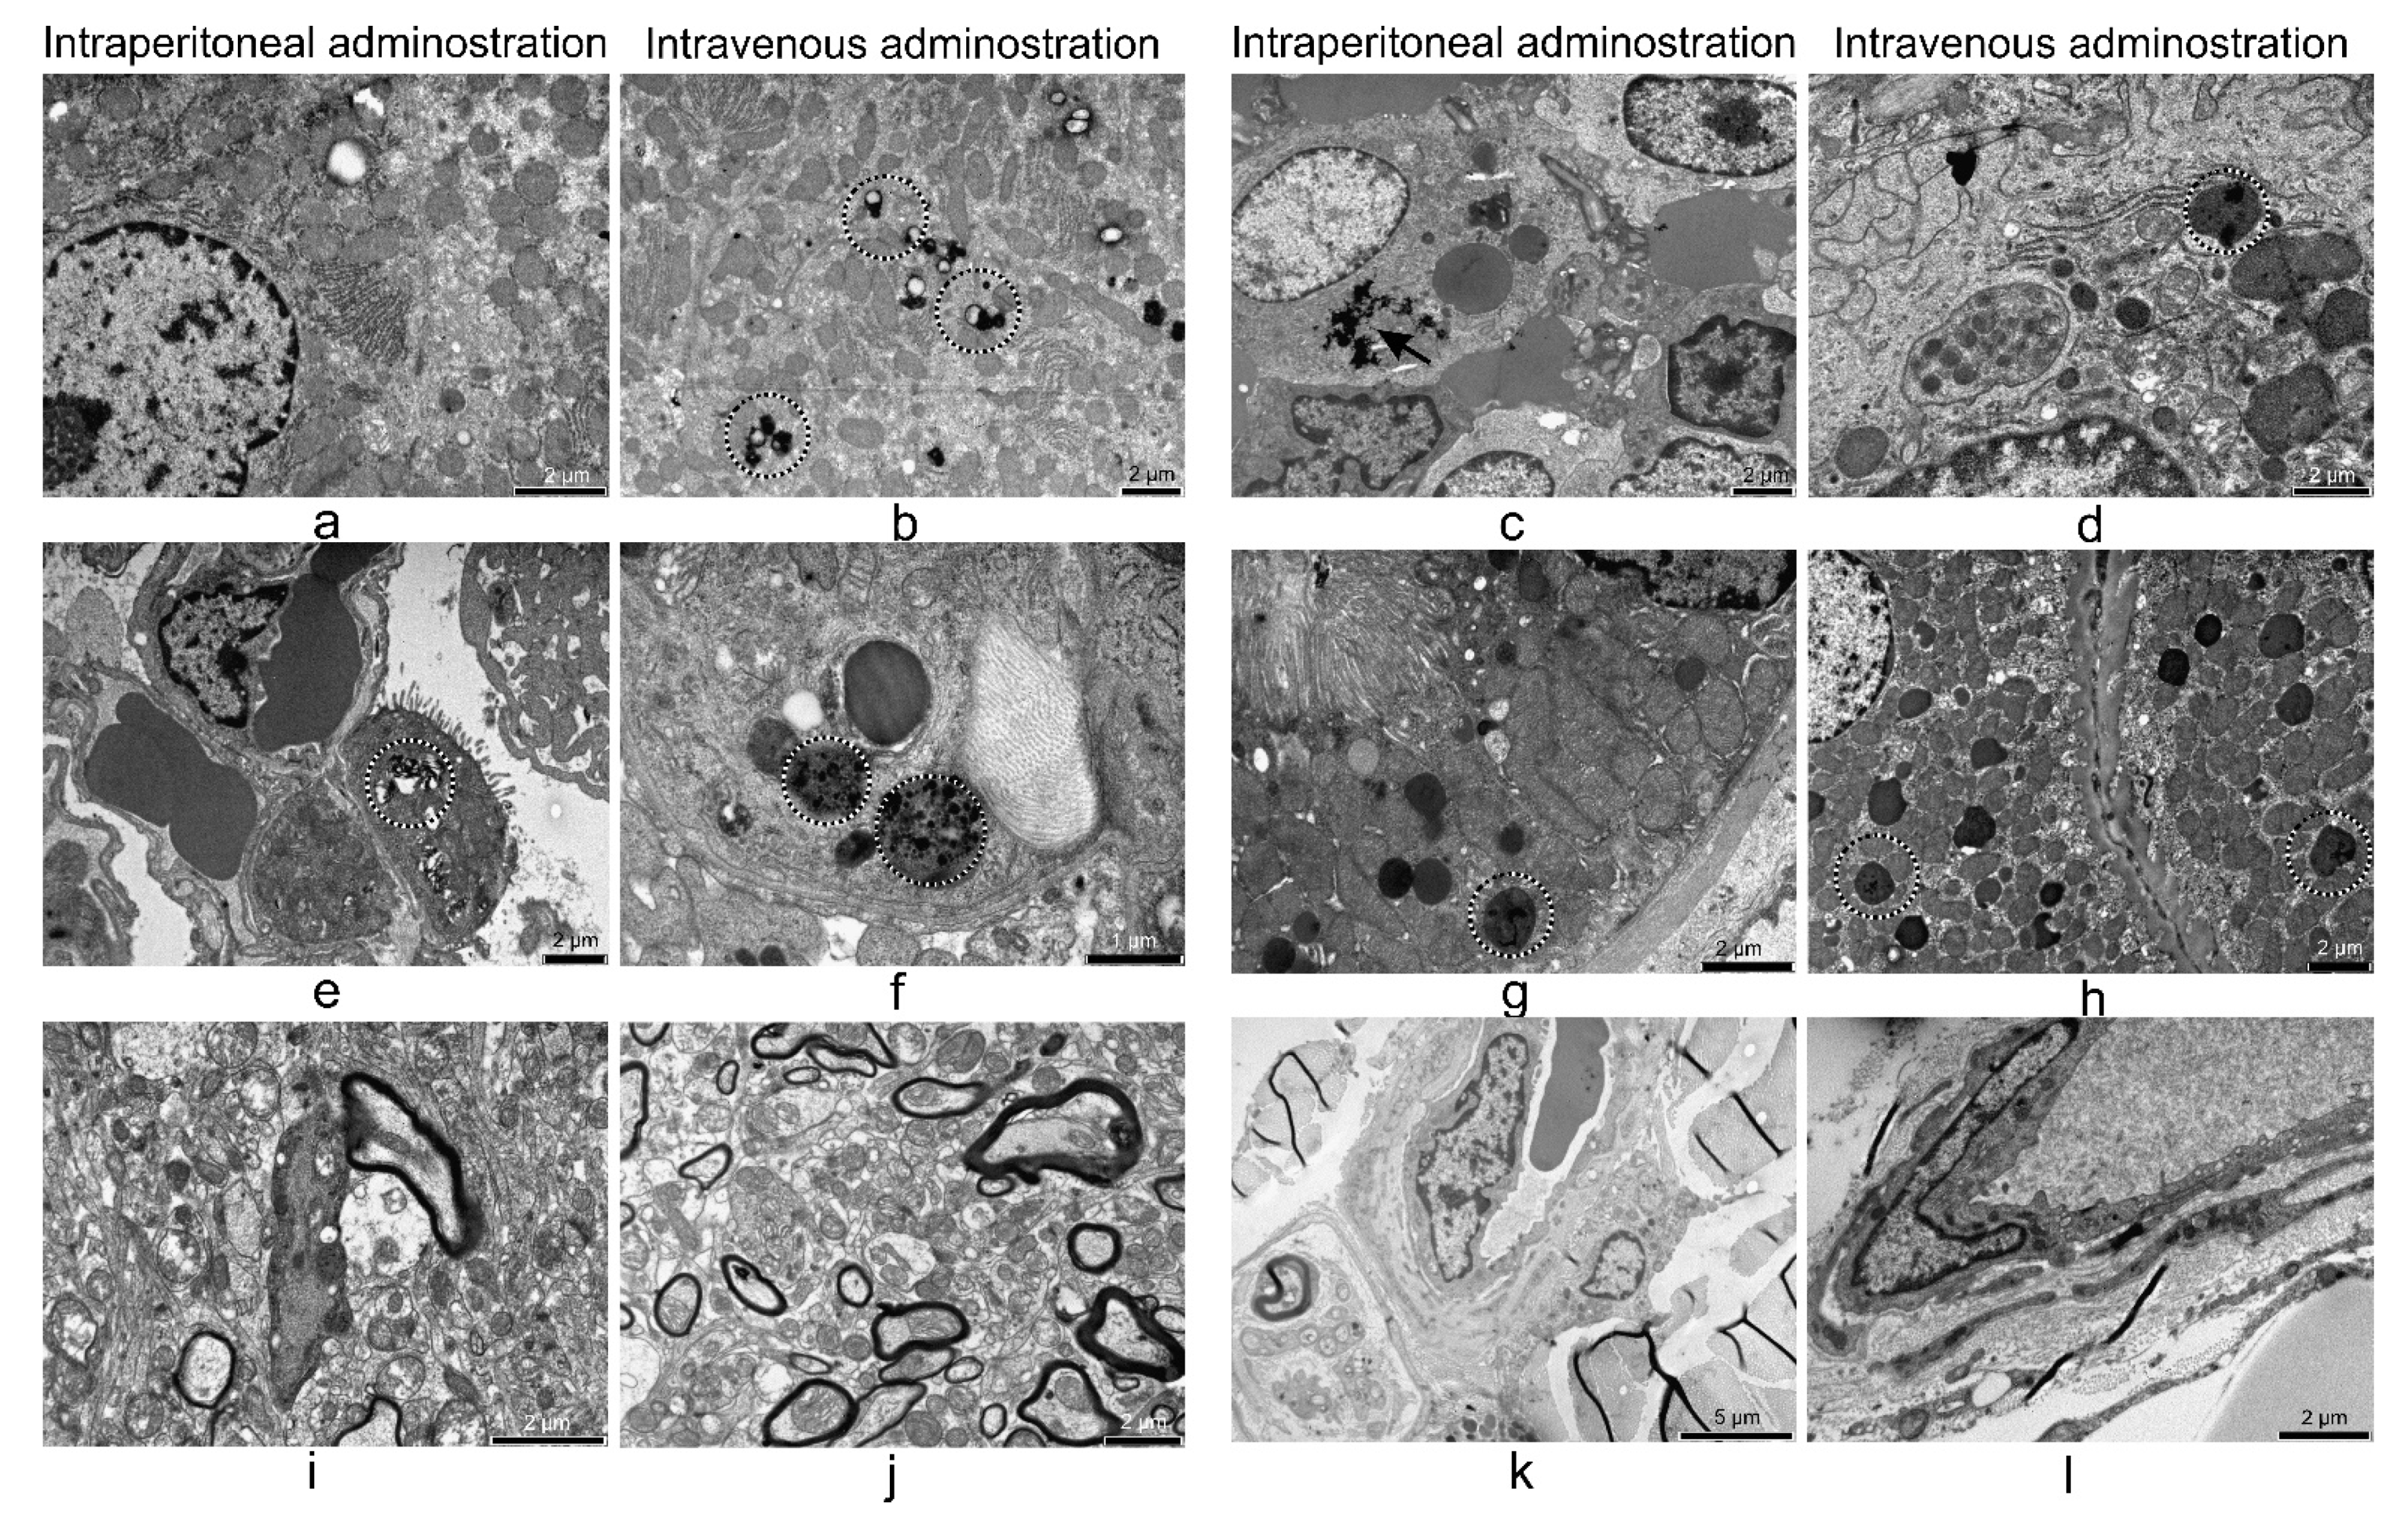

3.5. Electron Microscopy Analyses of Rat Organs

3.5.1. Liver

3.5.2. Lung

3.5.3. Kidney

3.5.4. 24 h after i.p. and i.v. Treatment